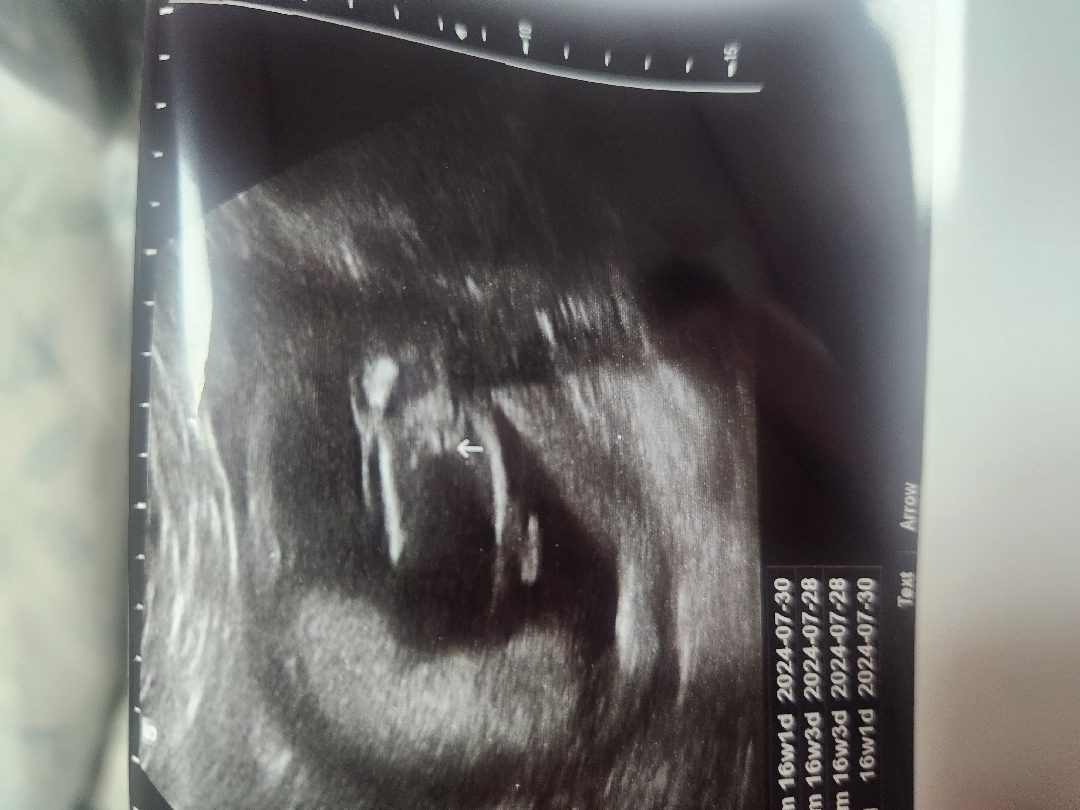

저희아기 딸인가요?아들인가요?

16주2일차인데 오늘병원가서봤는데ㅎ 딸인것같나요?아들같나요??ㅜㅜ 의견여쭤보고싶어요ㅎ

20주에 반전되는 경우도 있다고는 하는데 남아들 초음파 사진보면 워낙 존재감이 뚜렷하더라구요ㅎㅎ

딸인 것 같아요~ 저도 오늘 16주차라 초음파 보고 왔는데 비슷했어요ㅎㅎ 선생님이 안보인다고, 딸일 확률이 높다고 하시더라구요~